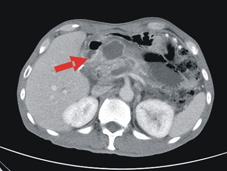

有關胰臟炎康復的病人,該如何健康保養與追蹤呢?對於急性胰臟炎的病人,在復原以後建議3至6個月內安排腹部超音波追蹤,尤其是一開始即有腹水形成的患者,因為這些人有較高的比例會發生胰臟炎的後續併發症,例如:偽囊腫(pseudo-cyst) (圖三)。一旦形成便需要視情況做必要的處理。另一方面,慢性胰臟炎是得胰臟癌或各式各樣胰臟腫瘤的危險因素之一,所以這類病人應該定期接受腹部超音波或內視鏡超音波的追蹤,以達到能早期發現胰臟腫瘤 (圖四)的目的。

圖三、箭頭處是指有顯影劑的電腦斷層下之胰臟偽囊腫